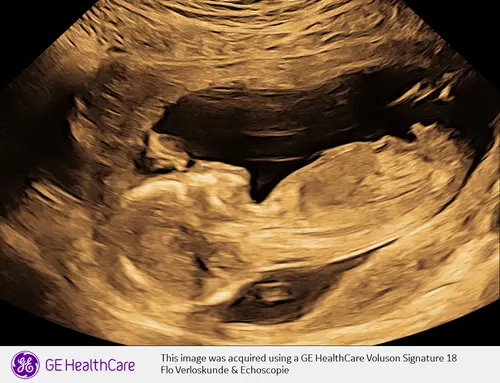

Vanaf 13+0 had vandaag geslachtsecho en was zo duidelijk en mooi!! Jongetje🩵🩵🩵